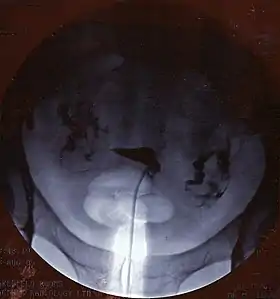

![]() A normal hysterosalpingogram. Note the catheter entering at the bottom of the screen, and the contrast medium filling the uterine cavity (small triangle in the center). | |